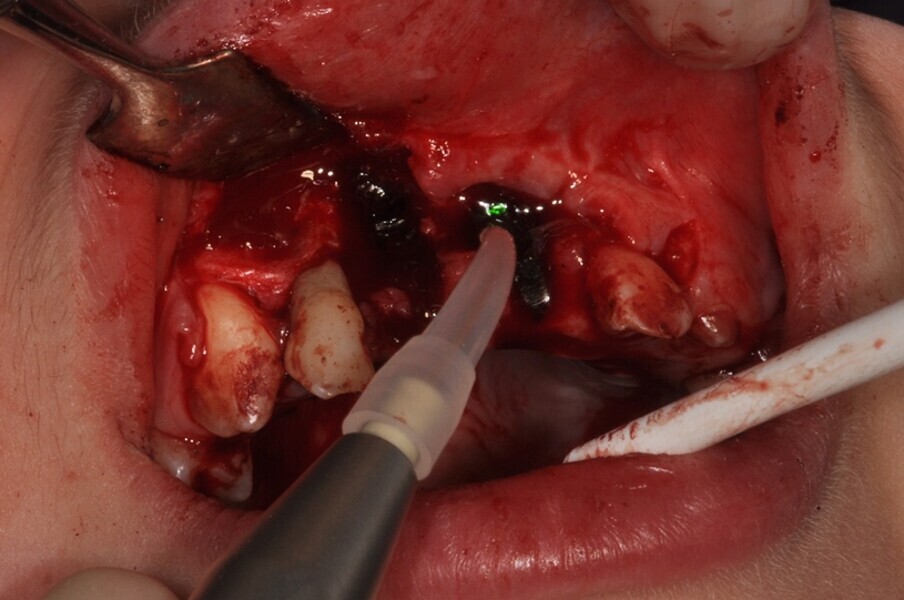

Ryc. 4¬_Stan miejscowy po ekstrakcji i ablacji kości.